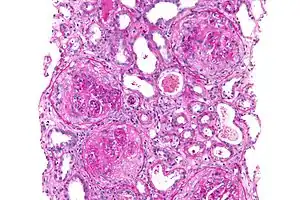

| Micrograph of a crescentic glomerulonephritis due to GPS, PAS stain | |